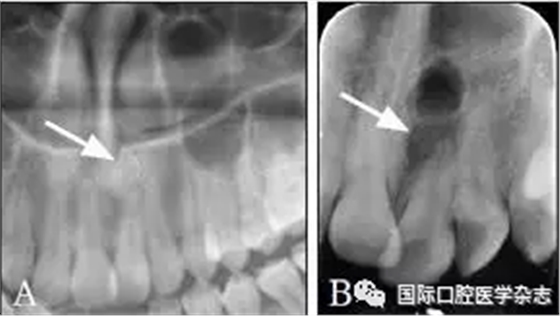

典型病例6 患者的CBCT圖像顯示上下頜骨多發(fā)性的低密度透射區(qū),但牙根完整,未見明顯吸收,牙齒仍有活力(圖6)。

A:矢狀位;B:水平位。

圖 6 骨結(jié)構(gòu)不良的CBCT圖像

Fig 6 CBCT of osseous dysplasia